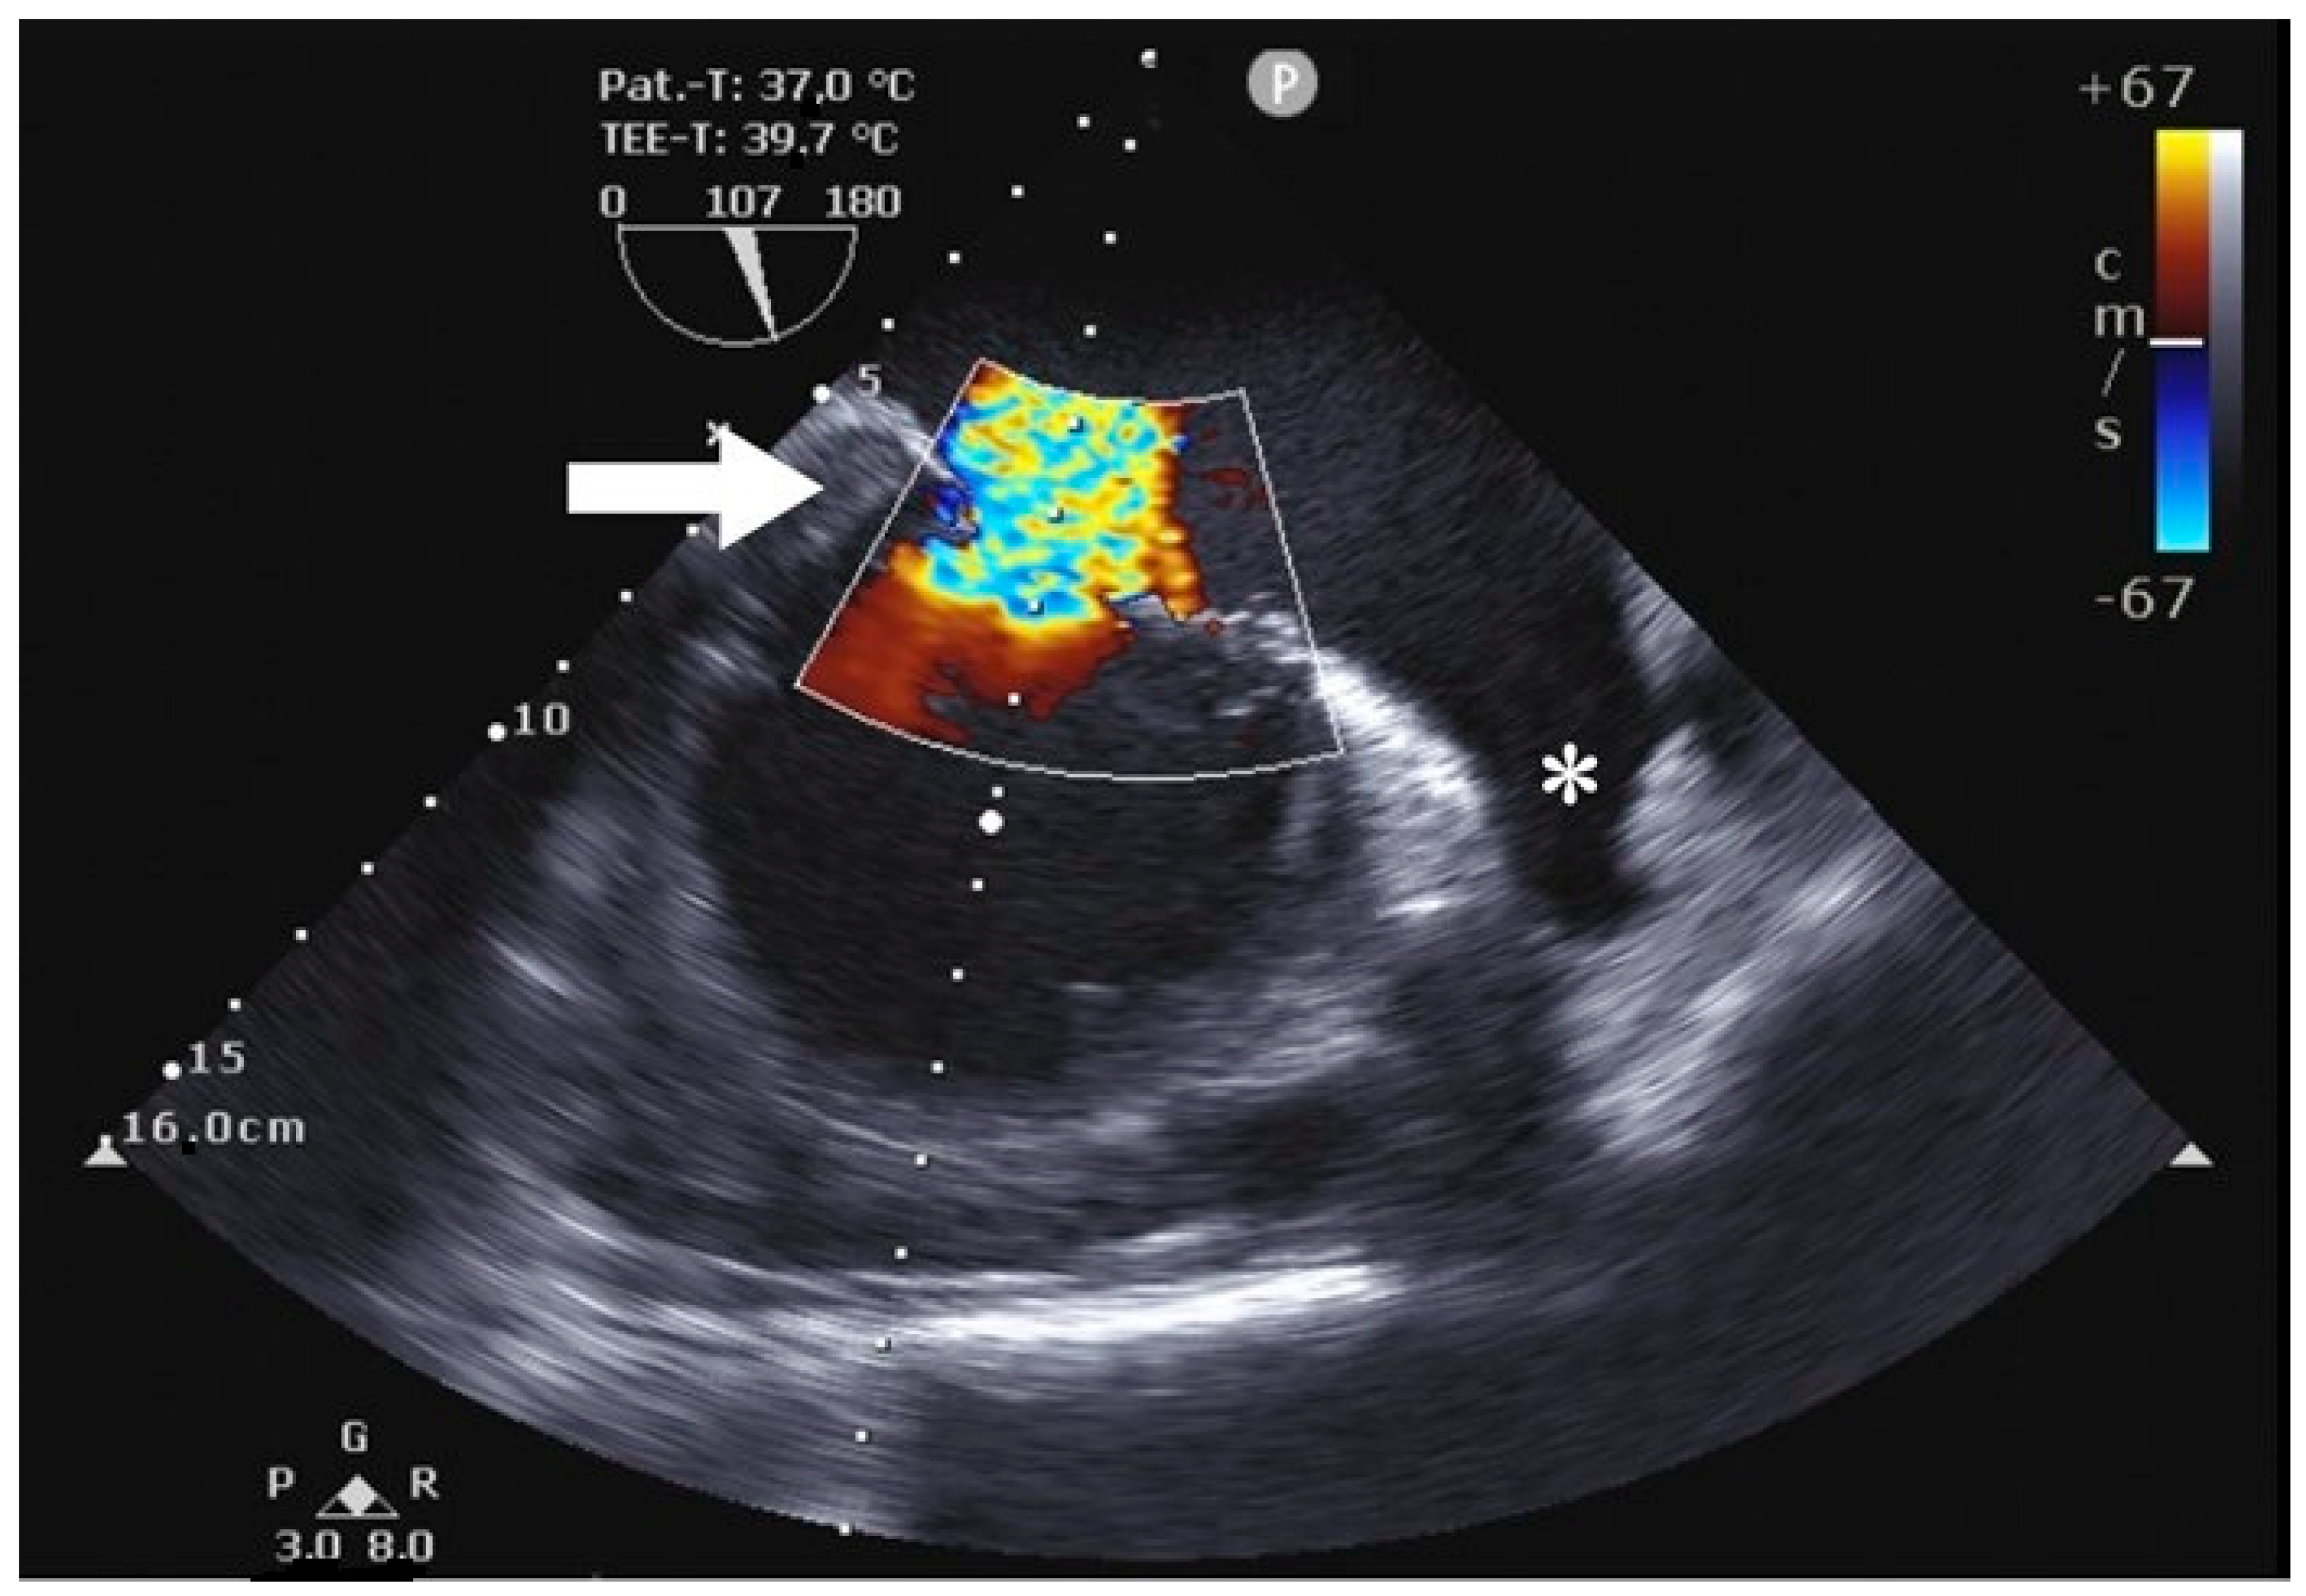

Preoperative transesophageal echocardiography (TEE) showed severe mitral valve regurgitation with an eccentric regurgitant jet, a flail of the medial portion of the A3 segment, and a prolapse of the A3 segment. The vena contracta (VC) at 9–10 mm had an estimated effective regurgitant orifice (ERO) of 0.5 cm2 and an estimated regurgitation volume (RV) of 95 mL. Additionally, there was a prolapse in the septal tricuspid valve leaflet with severe tricuspid regurgitation, a VC of 9 mm × 10 mm, an estimated ERO of 0.4 cm2 and an estimated RV of 53 mL. The right ventricular ejection fraction was within the normal range.

Using the AtriCure® (AtriCure, Mason, OH, USA) measuring device, the LAA base size was measured. After bending the AtriClip-Pro® (AtriCure, Mason, OH, USA) device, the clip was anteriorly passed over the LAA apex, gently compressing the great arteries and exposing the LAA. With a beating heart, the Atriclip-Pro® (AtriCure, Mason, OH, USA) was adequately placed under TEE guidance (Figure 4 and Figure 5), and the device was released after the confirmation of LAA closure (Figure 6 and Figure 7; Supplementary Video S1).

Figure 4. Preoperative transesophageal echocardiography showing severe mitral valve regurgitation (arrow) as well as the LAA (*).